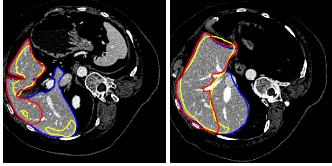

Refer to caption

Figure 7: 2D images of segmentation results of four challenging cases in axial, sagittal, and coronal planes with the ground truth in blue. The initial liver region generated by CNNs is in yellow and the final refined result is in red

Figure 8: 3D visual representation of livers segmented by our method on the same four cases as shown in Fig. 7. The first row shows the ground truth; the second and third rows present the surface distance error (mm) of 3D CNNs and the proposed segmentations with the ground truth

Figure 7 illustrates our segmentation and manual delineations for four challenging cases in coronal, sagittal, and axial planes. The initial liver region generated by 3D CNNs is in yellow, the final refined result is in red and the manual delineation is in blue. The first column shows a case with highly inhomogeneous appearances. The last three columns display three representative livers containing tumors. Particularly, some tumors locate on the boundary, which makes it more difficult to automatically delineate the accurate boundary. As can be seen, 3D CNNs can detect the most liver region and the refinement model can obtain a higher agreement with the ground truth. Figure 8 depicts the corresponding 3D visualization results of 3D CNNs and the proposed method for the cases shown in Fig. 7. The 3D visualization of errors is based on the MSD error between the segmentation result and the ground truth. As can been seen, the MSD errors of the 3D CNNs for the four cases (from left to right) are 22.1 mm, 12.6 mm, 62.6 mm and 74.5 mm, respectively, while the MSD errors of the proposed model are 17.0 mm, 11.2 mm, 22.1 mm and 15.3 mm, respectively. Obviously, the proposed approach can obtain lower errors in terms of MSD.